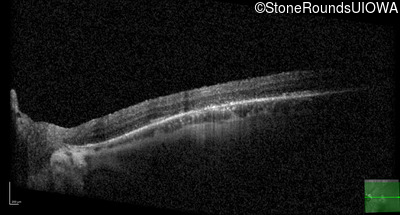

XL Cone and Cone Rod Dystrophy (IA1bi)

XL Cone and Cone Rod Dystrophy (IA1bi)

This 52 year old man had normal vision until his mid 30's when he began to have trouble distinguishing colors. the issuing 10 years he had a gradual loss of visual acuity accompanied by increasing photophobia.

| XL Cone and Cone Rod Dystrophy | RPGR | Gly1093 del2gGA | XL |